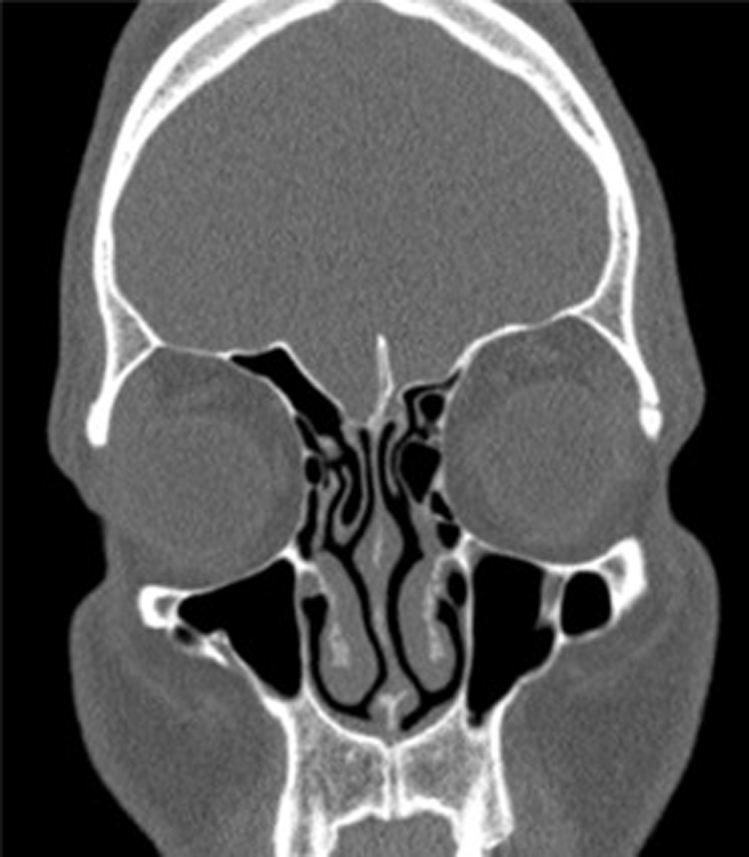

Age, gender, physical examination findings, and right and left ethmoid roof depths of the patients were measured. In order to evaluate the roof asymmetry of the patients, measurements were made by comparing the right and left coronal plane and calculating the distance. The depth of the lateral coverslip was calculated by subtracting the depth of the cribriform plate from the depth of the medial roof (Fig. 1). The measurements of our patients were taken from the first section of the infraorbital nerve from the coronal CT images, and a comparison was made between the groups.

Figure 1.

Etmoid roof asymmetry and concha bullosa. Unilateral concha bullosa and ethmoid roof asymmetry are evident. Coronal section the paranasal sinus CT image is the section where the infraorbital nerve was first seen, and all measurements were taken from this section.